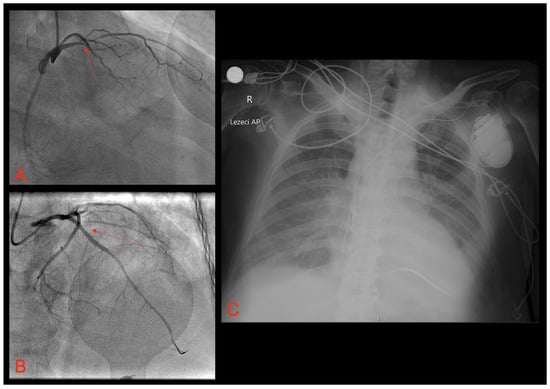

2. Case Report